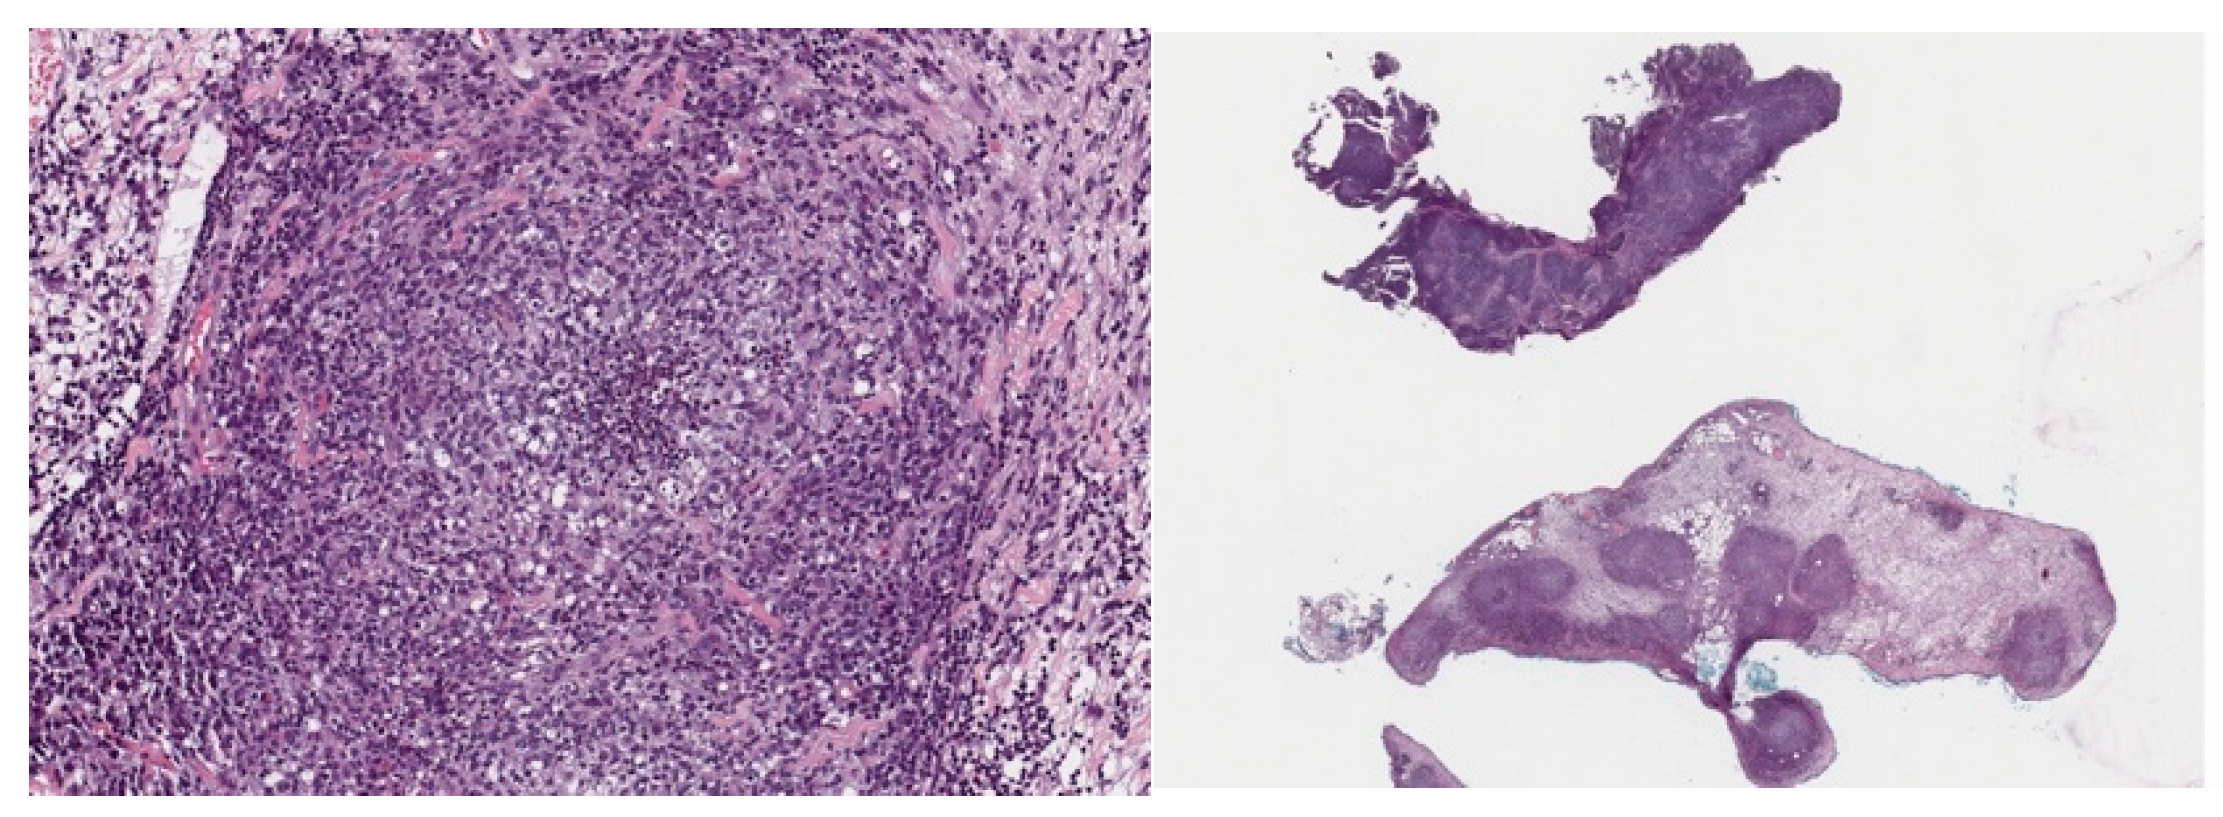

3.1. Case 1